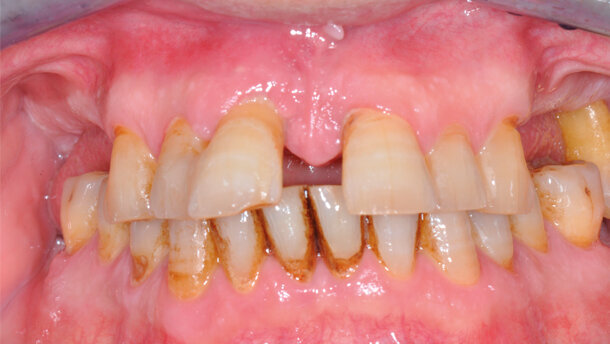

S.F., di 57 anni, si presenta presso la nostra struttura lamentando difficoltà alla masticazione, mobilità degli elementi dell’arcata superiore e sensazione che questi “si siano progressivamente spostati verso l’esterno”. All’anamnesi si registra un episodio di cardiopatia ischemica avvenuto tre anni prima, attualmente trattato con terapia antiaggregante orale. All’esame clinico e radiografico si presenta un quadro di parodontite cronica avanzata con migrazione patologica degli elementi dentari e riduzione della dimensione verticale. Il paziente è edentulo bilateralmente distale ai canini, eccezion fatta per un 27 con mobilità di terzo grado. Riferisce pregressi ascessi in corrispondenza dei due incisivi di destra, che presentano tasche oltre i dieci millimetri e suppurazione al sondaggio. L’arcata inferiore mostra un quadro parodontopatico meno grave, con perdita dei secondi molari (Figg. 1-3).